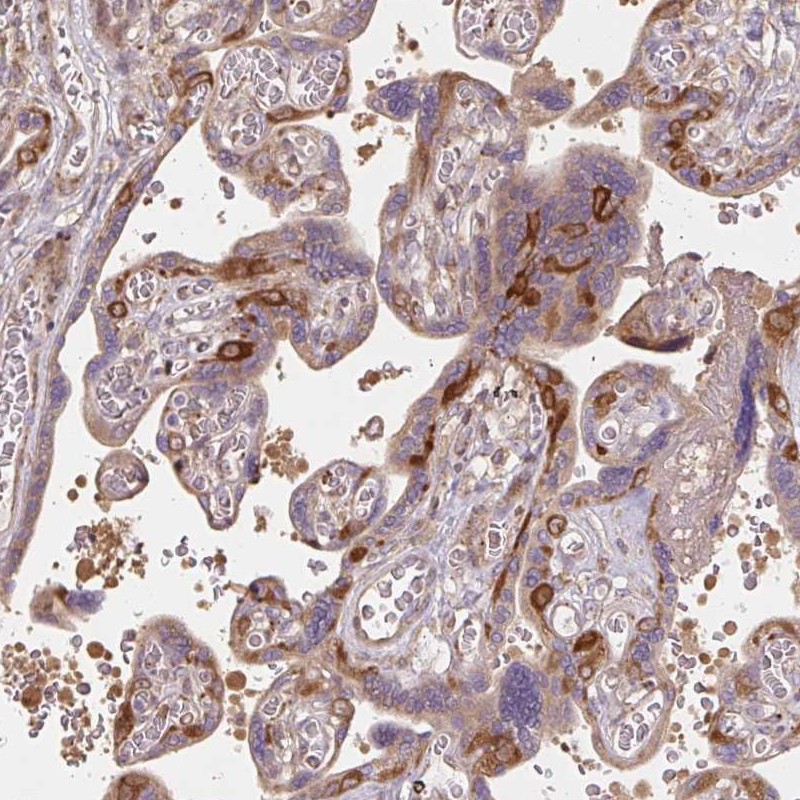

Immunohistochemistry analysis in human placenta and pancreas tissues using Anti-RASA1 antibody. Corresponding RASA1 RNA-seq data are presented for the same tissues.